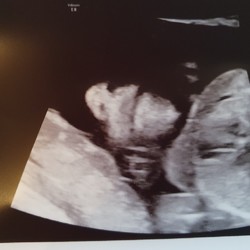

Ik ben sinds gisteren terug thuis na drie dagen in het ziekenhuis. Ik was vrijdag binnen gegaan met licht bloedverlies en op de monitor zagen ze dat ik contracties had. Ik was vrijdag 26+5 zwanger. Mijn baarmoedermond meette nog maar tussen de 1.3 en 1.7 cm. Ze zijn dan gestart met weeënremmers en long rijpers. Die hebben gelukkig hun werk gedaan en de baarmoedermond is terug iets bijgetrokken tot 2.3 cm. Nu moet ik 3x per dag utrogestan innemen en volledig platte rust houden. Over een weekje terug op controle voor een nieuwe meting.